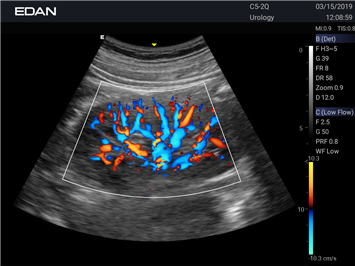

- Machine Type 4D Colour Doppler Ultrasound Machine

- Adaptive Doppler imaging Frequency Compounding Imaging ,- Adaptive Spatial Compounding Imaging ,- Harmonic Imaging ,- Adaptive Speckle Reduction Imaging (eSRI)

- Spectrum Enhancement ,- B mode Auto Optimization ,- Color mode Auto Optimization

- PW mode Auto Optimization